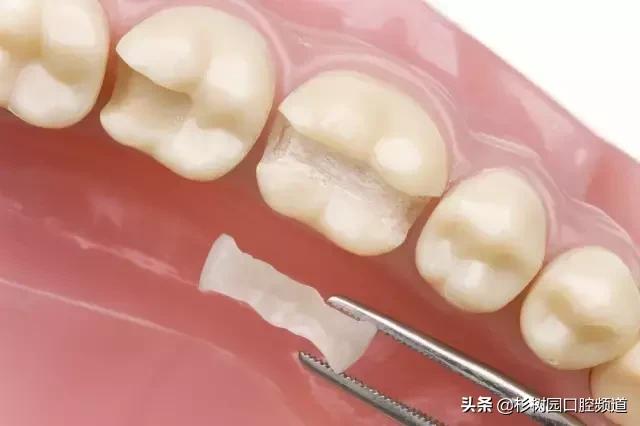

表面形态

不同的表面形态有助于纤维桩在根管内的固位和树脂核的固位,以下图片展示各种形态的纤维桩,大家可以根据自己的习惯加以选择。

如果后牙需要打多个纤维桩时要检查是否互相妨碍以及就位顺序等。

纤维桩使用数目要根据根管的粗细和牙体缺损范围来设计,可以在主尖周围放置辅尖。后牙一般按照牙体缺损范围来设计,一般2到4个足够了。

推荐将树脂核堆好之后再截断纤维桩,而不是截断后再粘接。如下图: